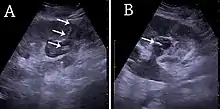

(A) Renal ultrasonograph of percutaneous nephrostomy tube placed through a calyx in the lower pole of a kidney with hydronephrosis. (B) The pigtail catheter is placed in the dilated calyx. The tube in (A) and the pigtail in (B) are marked with white arrows.[1]